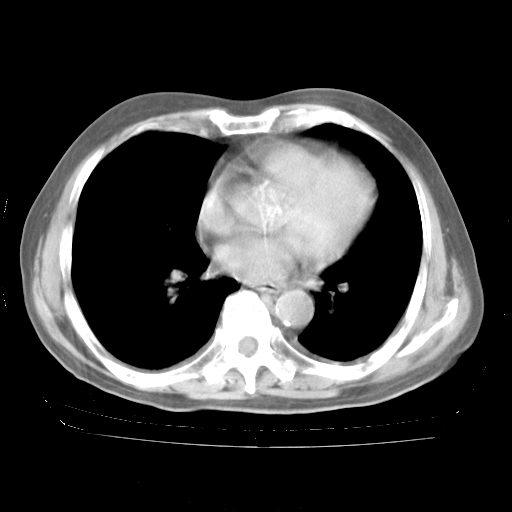

轻微咳嗽,无痰,(体温正常时)R20次/分,P75次/分,双肺底、腋下可闻及少量捻发音。下肢轻度浮肿。

ECG:右心室增大

心脏超声检查:无右心室增大。